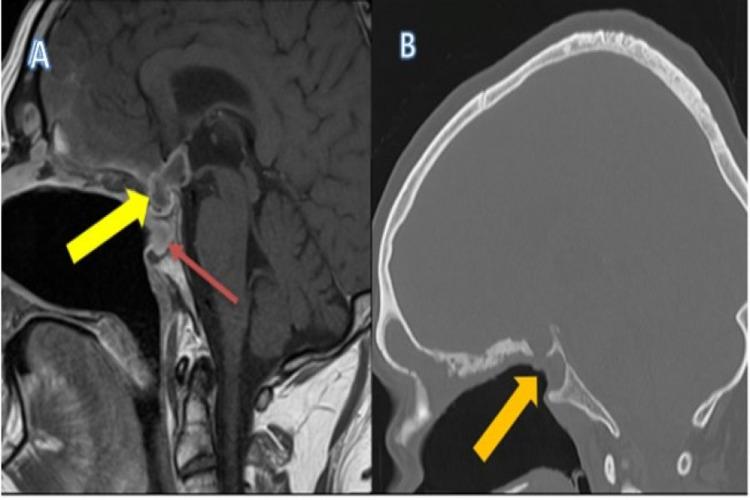

Cocaine is a well-known recreational drug with stimulant effects associated with relevant social, economic, and clinical implications. The most common route of abuse is via snorting. It has high addictive potential. Furthermore, one of the most well-known symptoms of a chronic user is chronic rhinitis. In the medical journals, there are numerous reports of complications, including lesions affecting the nasal septum, nasal sinuses, and even brain abscesses. We came across a 41-year-old male patient with severe manifestations of chronic cocaine use involving nasal, paranasal, and visual symptoms and signs. However, the most devastating was the complication of pituitary abscess, as a sequela to chronic cocaine sniffing. This case highlights the clinical, diagnostic, and management challenges with a multi-disciplinary approach. Last but not least, was the role of patient counselling and education. This ensured compliance towards management with a favourable outcome, which was rewarding for both the patient and the medical team involved in the care of the patient. It would hopefully create more awareness and assist in abstinence. We also hope it would incite more effort towards data collection and analysis, as well as allow us to explore the actual incidence of its use and devastating complications, which to date, for reasons of disguise and denial, remain somewhat ambiguous.

可卡因是一种广为人知的消遣性药物,具有刺激作用,会带来相关的社会、经济和临床影响。最常见的滥用途径是鼻吸。它具有很高的成瘾潜力。此外,慢性使用者最广为人知的症状之一是慢性鼻炎。在医学期刊上,有许多关于并发症的报道,包括影响鼻中隔、鼻窦甚至脑脓肿的病变。我们遇到了一名41岁的男性患者,他有慢性可卡因使用的严重表现,涉及鼻腔、鼻窦和视觉症状及体征。然而,最具破坏性的是垂体脓肿并发症,这是慢性可卡因鼻吸的后遗症。该病例凸显了采用多学科方法应对的临床、诊断和管理挑战。最后但同样重要的是患者咨询和教育的作用。这确保了患者对治疗的依从性,并取得了良好的结果,这对患者和参与患者护理的医疗团队来说都是值得的。这有望提高更多认识并有助于戒毒。我们还希望这能促使人们加大数据收集和分析的力度,并让我们能够探究其使用情况和破坏性并发症的实际发生率,迄今为止,由于伪装和否认等原因,这些情况仍有些模糊不清。